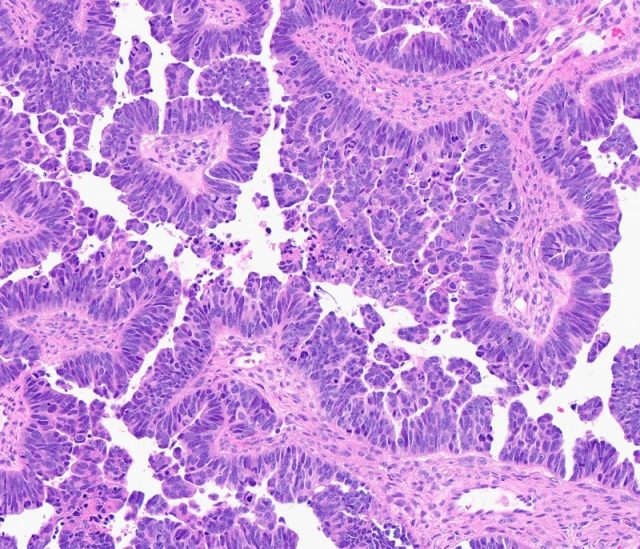

“È molto importante accreditare i sistemi modello dimostrando che riassumono le caratteristiche chiave delle loro controparti umane, un processo che richiede anche molto tempo”, ha affermato Cho, co-autrice senior dello studio, Professore di Patologia Peter A. Ward, co-direttore del programma di genetica del cancro del Rogel Cancer Center e direttore di Patologia Ginecologica presso la Michigan Medicine.

“Queste caratteristiche includono non solo l’origine cellulare e l’aspetto al microscopio, ma anche la tempistica dello sviluppo del tumore, la genetica sottostante, le alterazioni genetiche acquisite e i profili di espressione genica, il microambiente tumorale (inclusi i componenti delle cellule immunitarie) e altri aspetti del comportamento biologico”, ha affermato.